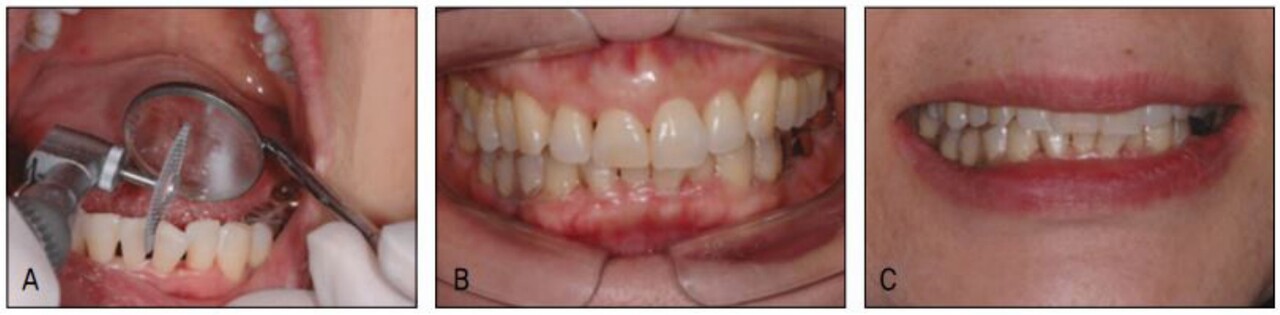

젊은 성인에서 치아가 움직이는 똑같은 기전으로 고령자 성인에서도 교정적 치아 이동이 가능하다. 다만 세포의 turn-over rate가 다소 느리므로 같은 거리 이동에 필요한 치료기간이 늘어날 수 있다. 그럼에도 불구하고 실제 치료기간은 그리 크게 증가 하지 않는 것을 볼 수 있다. 고령자 교정의 필요성이나 막대한 수요에도 불구하고 그동안 고령자 교정의 보급은 다소 늦은 감이 있는데 이는 교정치료 기간이라기 보다는 교정치료 시 불편감과 동통으로 인한 것이었다.

그러나 최근에는 불편감을 줄이기 위해 작은 크기(low profile)의 장치를 사용하고 동통을 줄이기 위해 미약한 힘(light force) 을 이용하는 테크닉들이 속속 개발되어 고령자 교정의 가능성 및 수월성이 크게 증가하였다. 수요의 증가에 맞는 교정치료 공급이 가능하게 된 바 고령자 교정은 폭발적으로 증가할 것으로 기대하고 있다.